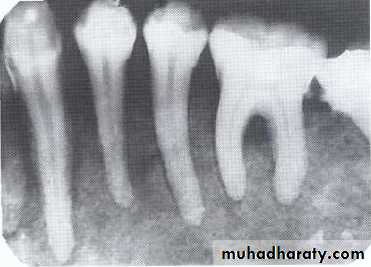

Radiolucency at apex of nonvital tooth

P. A. abscess

P. A. CystIs a cyst that remains after incomplete removal of the original cyst. The term residual is used most often for a radicular cyst that may be left behind, most commonly after extraction of a tooth.

*Persistent radiolucency in an area where a tooth has previously extracted.

• Residual cyst